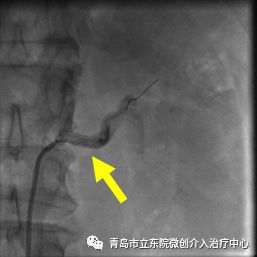

介入手术开始,穿刺患者右侧大腿的股动脉,通过2mm左右的穿刺孔送入导管,术中造影确认,左侧肾动脉重度狭窄。

确认肾动脉狭窄后,对病变进行球囊扩张并植入支架,肾动脉狭窄完全消失,血流恢复通畅。